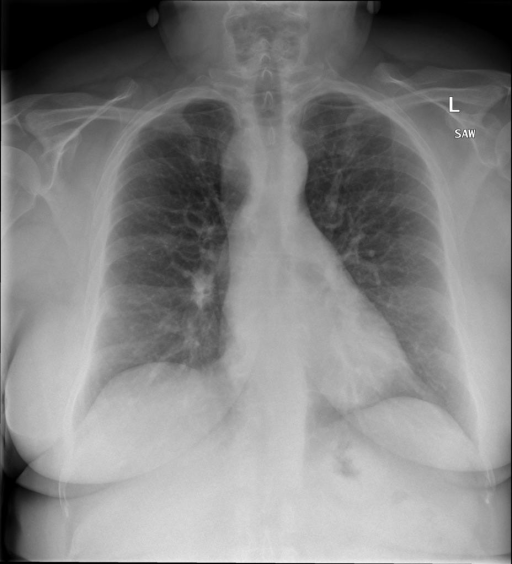

# 本文贡献  - 借助ChatGPT以及公开的数据集,我们构造了一个`X光影像-诊断报告`对的医学多模态数据集; # 数据集 - [MIMIC-CXR](https://physionet.org/content/mimic-cxr-jpg/2.0.0/)是一个公开可用的胸部X光片数据集,包括377,110张图像和227,827个相关报告。 - [OpenI](https://openi.nlm.nih.gov/faq#collection)是一个来自印第安纳大学医院的胸部X光片数据集,包括6,459张图像和3,955个报告。 在上述工作中,报告信息都为非结构化的,不利于科学研究。为了生成合理的医学报告,我们对两个数据集进行了预处理,并最终得到了可以用于训练的**英文报告**。除此之外,为了更好的支持中文社区发展,借助ChatGPT的能力,我们将英文报告进行了中文翻译,并最终形成了可用于训练的数据集。 |数据集|数量|下载链接| |:-|:-|:-| |MIMIC-CXR-zh|-|-| |OpenI-zh|6,423|[诊疗报告](./data/Xray/openi-zh.json) 、[X光影像](https://pan.baidu.com/s/13GBsDMKf6xBZBSHpoWH_EA?pwd=k9sh)| # 快速上手 1. 安装环境 ```bash # 安装依赖 pip install -r requirements.txt # 国内换源安装依赖 pip install -i https://mirrors.aliyun.com/pypi/simple/ -r requirements.txt ``` 此时默认会安装`deepspeed`库(支持`sat`库训练),此库对于模型推理并非必要,同时部分`Windows`环境安装此库时会遇到问题。 如果想绕过`deepspeed`安装,我们可以将命令改为: ```bash # 安装依赖 pip install -i https://mirrors.aliyun.com/pypi/simple/ -r requirements_wo_ds.txt # 安装SwissArmyTransformer pip install -i https://mirrors.aliyun.com/pypi/simple/ --no-deps "SwissArmyTransformer>=0.3.6" ``` 2. 模型推理 CLI推理: ```python python cli_demo.py --from_pretrained checkpoints/finetune-XrayGLM-05-25-01-04 --prompt_zh '详细描述这张胸部X光片的诊断结果' ``` 更多[参数](https://github.com/WangRongsheng/XrayGLM/blob/main/cli_demo.py#L16) # 效果展示 诊断: |X光影像|诊疗报告(医生)|XrayGLM| |:-|:-|:-| ||根据X射线图像,心脏大小正常,肺部看起来很清晰。已经排除了肺炎、积液、水肿、气胸、腺病、结节或肿块的存在。该发现表明一切正常。换句话说,总体印象是胸部正常。|X光片显示,心脏大小正常。肺部没有气胸或胸腔积液的证据。骨骼结构看起来没有任何异常。总的来说,X光片表明没有发现急性心肺疾病的迹象。| ||X光图片显示没有扭曲的区域、可疑的骨质不透明度或胸腺积液。心脏大小轻微增大,但非常稳定。此外,没有气胸的证据,肺野也正常。总体来说,X光片显示没有急性心脏异常,但要注意轻微的心脏扩大。|X光片显示,心脏大小正常。肺部和纵隔轮廓清晰,没有气胸或胸腔积液的证据。骨骼结构完整,没有任何急性异常。| ||心影形态在正常范围内。没有急性骨质异常。有可能出现没有明显的吸水或肺实质状况的线索。没有大面积积液或气胸。有可能怀疑其有误吸或肺实质问题。为了确诊和治疗,可能需要进行适当的影像学随访。|心脏大小正常,肺部和纵隔轮廓清晰。没有急性异常或活动受限的证据。没有任何明显的气胸、胸腔积液或肺不张的迹象。此外,也没有发现任何局灶性骨质异常或其他急性疾病。| 多轮对话: |X光影像|诊疗报告(医生)| |:-|:-| ||右侧主动脉突出观察到。心脏大小正常。胸部未发现明显的肺气肿、胸膜积液或可疑的肺部病变。报告指出已知右侧主动脉情况正常。| ```bash >> X光影像路径:./data/Xray/861_1.png >> 用户:这是一张什么图? >> XrayGLM:这张图片显示的是一张肺部检查的X光片。 >> 用户:请描述这张胸部X光片的诊断结果 >> XrayGLM:心脏大小正常,肺部清晰。没有急性心肺疾病的证据。 >> 用户:是否存在肺气肿? >> XrayGLM:没有肺气肿。心脏大小正常,肺部清晰。没有发现急性心肺疾病的证据。 >> 用户:平时饮食该注意什么? >> XrayGLM:饮食应该健康,均衡。建议增加蛋白质的摄入量,因为蛋白质有助于维持肌肉和骨骼的健康。多食用蔬菜、水果、全谷物以及健康的脂肪来源如橄榄油、鱼类等可以帮助获得足够的维生素和矿物质。此外,避免过度饮酒或吸烟,这些习惯可能会对心脏健康产生负面影响。 ``` # 项目致谢 1. [VisualGLM-6B](https://github.com/THUDM/VisualGLM-6B)为我们提供了基础的代码参考和实现; 2. [MiniGPT-4](https://github.com/Vision-CAIR/MiniGPT-4)为我们这个项目提供了研发思路; 3. ChatGPT生成了高质量的中文版X光检查报告以支持XrayGLM训练; 4. [gpt_academic](https://github.com/binary-husky/gpt_academic)为文档翻译提供了多线程加速; 5. [MedCLIP](https://github.com/RyanWangZf/MedCLIP) 、[BLIP2](https://huggingface.co/docs/transformers/main/model_doc/blip-2) 、[XrayGPT](https://github.com/mbzuai-oryx/XrayGPT) 等工作也有重大的参考意义;  这项工作由[澳门理工大学应用科学学院](https://www.mpu.edu.mo/esca/zh/index.php)硕士生[王荣胜](https://github.com/WangRongsheng) 、[段耀菲](https://github.com/IsBaSO4) 、[李俊蓉](https://github.com/lijunrong0815)完成,指导老师为檀韬副教授、[彭祥佑](http://www.patrickpang.net/)老师。 *特别鸣谢:[USTC-PhD Yongle Luo](https://github.com/kaixindelele) 提供了有3000美金的OpenAI账号,帮助我们完成大量的X光报告翻译工作 # 免责声明 本项目相关资源仅供学术研究之用,严禁用于商业用途。使用涉及第三方代码的部分时,请严格遵循相应的开源协议。模型生成的内容受模型计算、随机性和量化精度损失等因素影响,本项目无法对其准确性作出保证。即使本项目模型输出符合医学事实,也不能被用作实际医学诊断的依据。对于模型输出的任何内容,本项目不承担任何法律责任,亦不对因使用相关资源和输出结果而可能产生的任何损失承担责任。 # 项目引用 如果你使用了本项目的模型,数据或者代码,请声明引用: ```bash @misc{wang2023XrayGLM, title={XrayGLM: The first Chinese Medical Multimodal Model that Chest Radiographs Summarization}, author={Rongsheng Wang, Yaofei Duan, Junrong Li, Patrick Pang and Tao Tan}, year={2023}, publisher = {GitHub}, journal = {GitHub repository}, howpublished = {\url{https://github.com/WangRongsheng/XrayGLM}}, } ``` # 使用许可 此存储库遵循[CC BY-NC-SA](https://creativecommons.org/licenses/by-nc-sa/4.0/) ,请参阅许可条款。